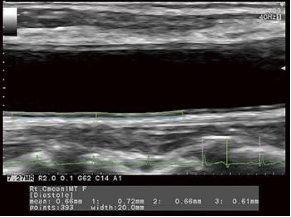

Автоматический расчет комплекса интима-медиа

Система помогает выполнить сосудистые, кардиологические, акушерско-гинекологические расчеты.

Она упрощает работу врача и исключает риск врачебной ошибки.